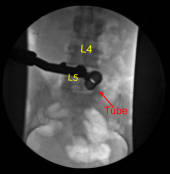

A 22-gauge spinal needle was used to localize the L5-S1 level. A marking pen was used to demarcate the midline. An 18 mm vertical incision adjacent to the spinous process on the right side was demarcated. 1% lidocaine with epinephrine was infused.

The skin was opened with a #15 blade scalpel. Hemostasis was obtained with Bovie. Bovie was used to sharply divide the fascia. Sequential dilators were used to dock a 16 mm diameter x 4 cm tubular retractor which was affixed rigidly to the bed frame.

The herniated disc fragments were collected and sent to pathology for analysis. An annular defect was identified and extended with a bayoneted #15 blade scalpel.Neurolysis was performed with micro instruments of the S1 nerve root enabling sufficient retraction to fully remove the multiple herniated disc fragments until circumferentially the S1 nerve root was completely decompressed as well as the ventral thecal sac. This was confirmed with nerve hooks, Penfield micro instruments and fluoroscopy.